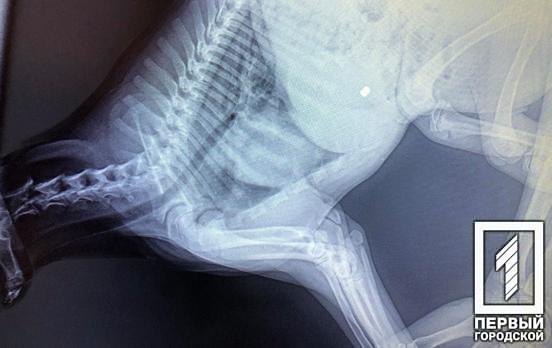

27 лютого близько 15:30 у Довгинцівському районі сталася непередбачена пригода. Там на одному з блокпостів військові вимушено розстріляли городян. Сталося все, за попередньою інформацією, через те, що водій автомобіля Toyota Land Cruiser, який, як то кажуть, в'їжджав на величезній швидкості на територію Військового містечка, що неподалік від аеродрому. Водій не виконав вказівки військовослужбовців зупинитися. При цьому чоловіки, що перебувають у салоні автомобіля, не дали військовим провести огляд авто (як і належить, на пропускному пункті, тим більше в умовах війни) і нібито пригрозили зброєю перевіряючим. Через таку непокору та опір бійці блокпоста відкрили вогонь по городянах. В результаті – смертельний результат. Розслідуванням цієї справи займатиметься військова прокуратура. З'ясувалося, що одним із смертельно поранених виявився відомий у певних колах Ельдар Махмудов.